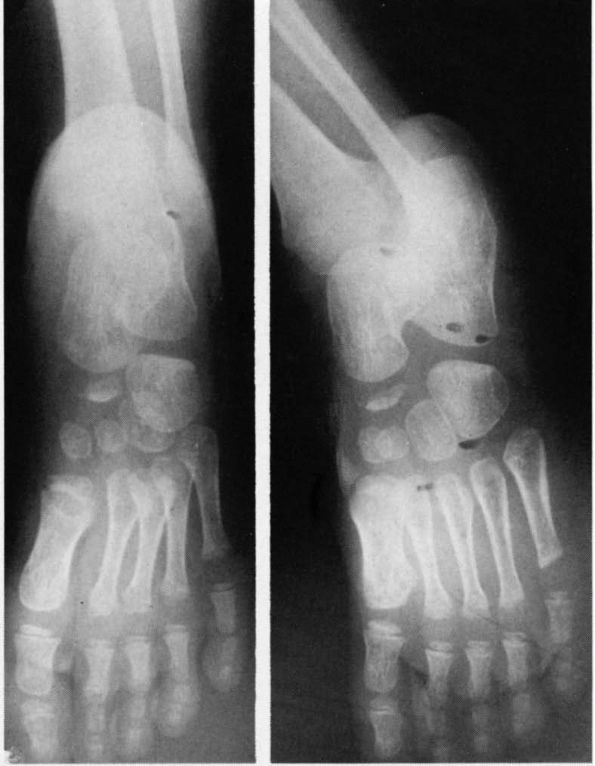

![]() |

FIGURE 20-27. Freiberg infarction (osteochondrosis of the metatarsal head). (A)

Frontal view of the resected metatarsal head. The articular cartilage is irregular with areas of loss of articular surface. There are multiple indentations about the head. The capsule about the periphery is thickened, and secondary osteoarthritic spurs are present. A cleft at the margin suggests formation of a loose body by separation. (B and C) Radiographs of the second metatarsal head before resection showing sclerosis, irregularity, widening, and spurring with flattening. |